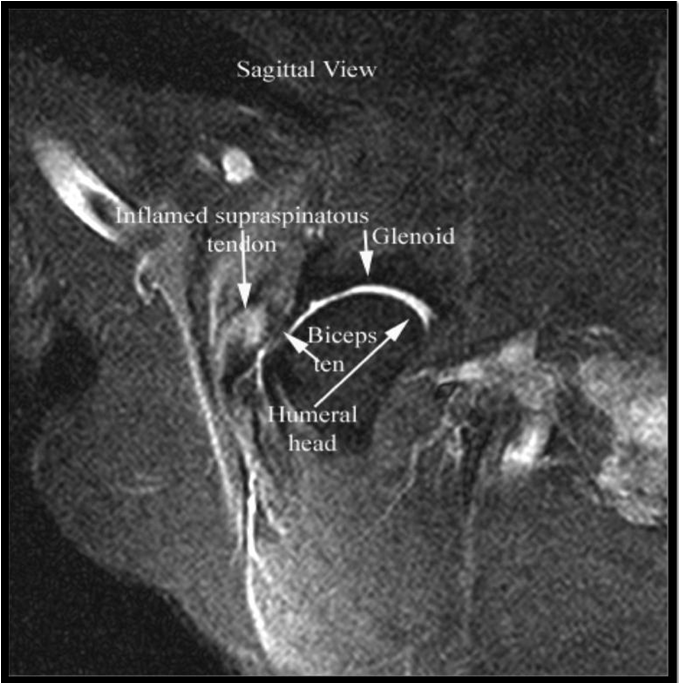

Supraspinatus Tendinopathy in 327 Dogs A Retrospective Study Canapp